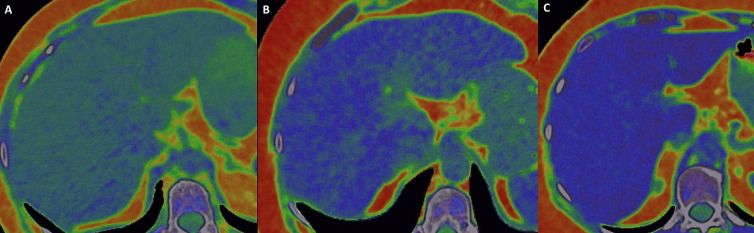

In comparison to primary lung cancer, pulmonary metastases had a 33 percent higher frequency of ring-like peripheral high iodine concentration on dual-energy computed tomography (DECT), according to a new retrospective study.